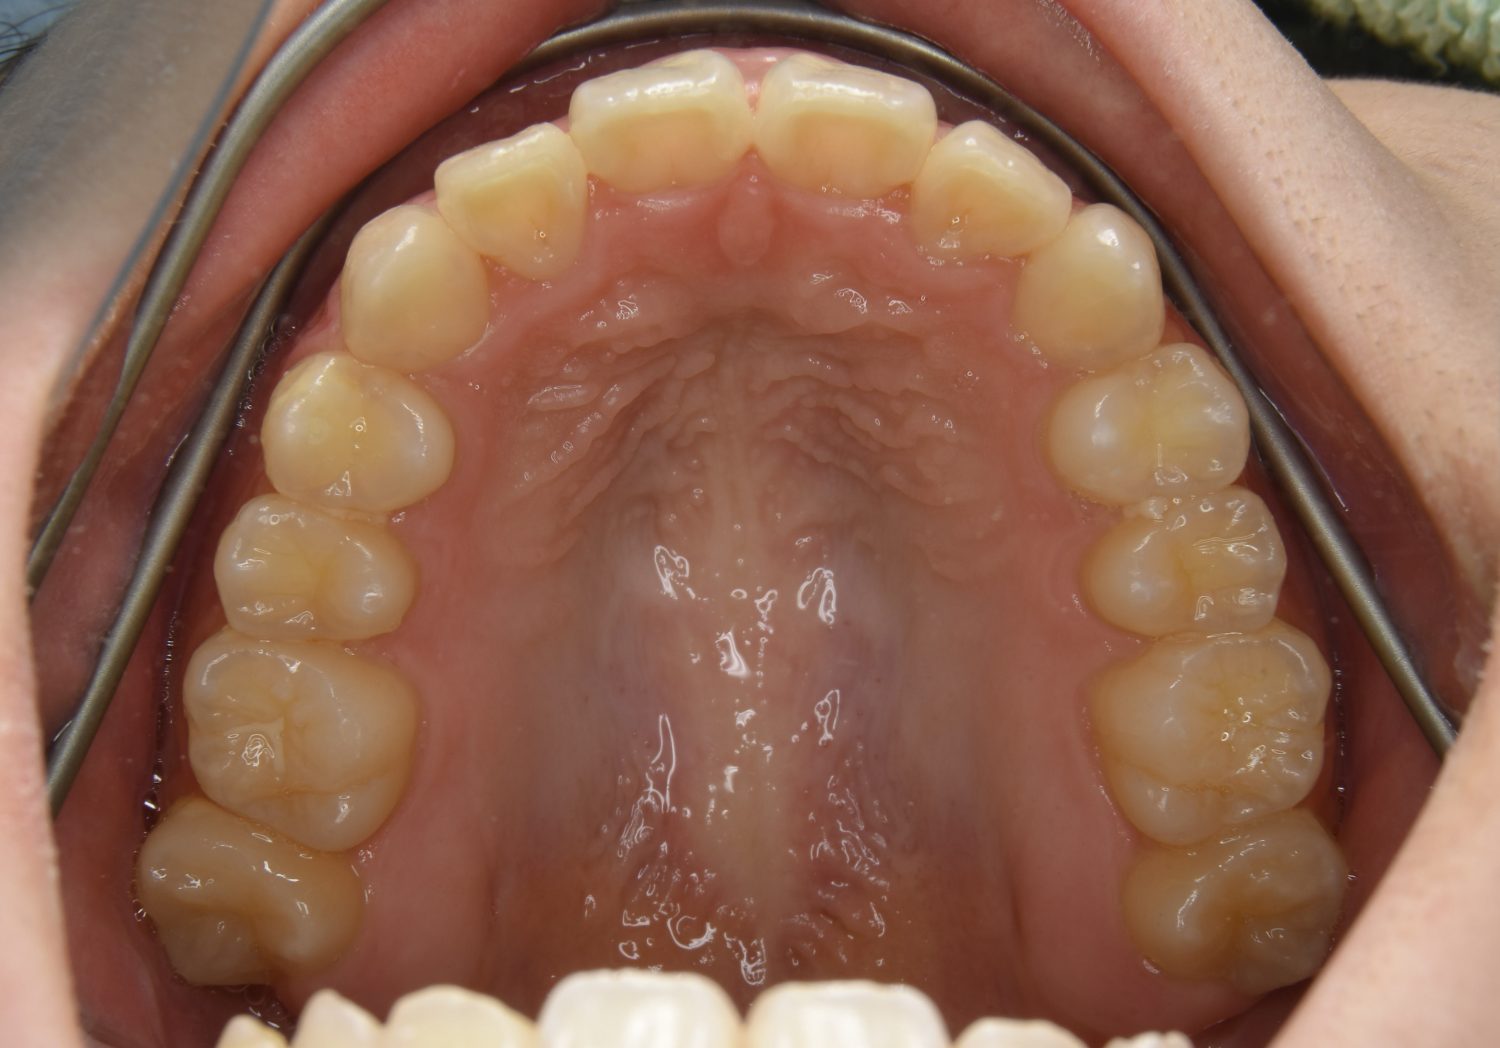

叢生の症例紹介①

Before

After

主訴

前歯のガタガタが気になる。

治療内容

上顎左側第一小臼歯を抜歯し、アライナー(インビザライン)にて治療を行いました。

治療費

1,150,000 円(税込)

治療期間

23ヶ月

通院回数

13回

想定されたリスク

※歯根吸収、歯肉退縮、歯髄壊死、顎関節症状

※アライナー(インビザライン)は日本の薬機法未承認の矯正装置であり、医薬品副作用被害救済制度の対象外となる場合があります。

丸山和宏先生

ピーススマイル矯正歯科

左上の側切歯が完全に内側に入り込んでいる状態でした。左上の第一小臼歯のみ抜歯を行い治療を行うことで機能面および審美面を改善しました。